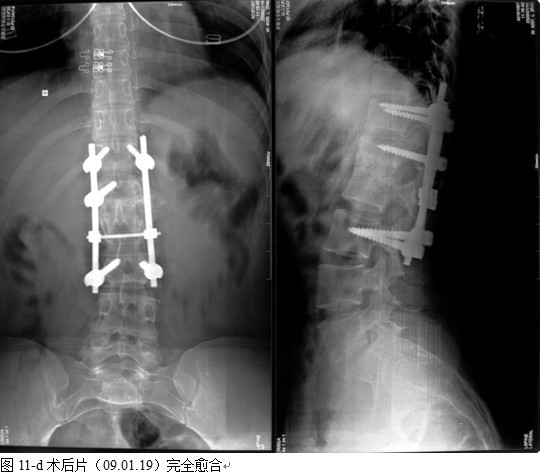

结果: 术后所有患者均显示,骨性融合, 马尾神经损伤的患者均基本恢复正常,术后后凸畸形平均矫正90%以上, 3-49个月的随访,后凸角度平均丢失4.2°。

本组手术用时间3~4h , 平均3.5h 。术中出血300~500ml , 平均约350ml 。术后症状完全缓解,无神经功能障碍加重等并发症,1例营养差的老年患者伤口出现窦道,1例因肝功能差,术后未口服抗痨药,伤口出现窦道,经换药后二期愈合,其余病例伤口均一期愈合。马尾神经受损的患者术后基本恢复正常。术后一周后凸角平均 5.4°后凸畸形平均矫正90%以上, 最终后凸角平均8.3°,后凸角度平均丢失4.2°。随访3个月有87%(40/46)有骨痂形成,6个月91.3%(42/46)明显骨性愈合(见图),其余4例9-12个月内愈合,随访时间3-32个月,平均11个月,46例患者中2例在术后2个月和3个月时背部形成脓肿,换药后治愈。2例出院1月后并发结核性脑膜炎,治疗后好转。1例因椎弓根钉偏外,刺激神经根,5个月后从侧方脱出,疼痛加重,因前后路植骨完全愈合,取出后症状完全缓解。

中国学者金大地[22]等采用一期前路病灶清除植骨前路钢板固定治疗腰椎结核,平均18°的后凸畸形得以矫正,Mukhtar[23] AM等采用前路病灶清除植骨分期或同期后路固定治疗腰椎结核22例,术后后凸畸形矫正度数平均为27°。从我们的随访结果看,术后后凸畸形平均矫正度数为26.9°,后凸畸形平均矫正90%以上, 6个月-49个月后随访,后凸角度平均丢失4.2°。本术式也适用于结核所引起的弹性差的后凸畸形,对于病灶纤维化或骨化的非弹性后凸畸形,后路固定后,先行前路病灶、纤维化或骨化切除、松解,逐步刮除病灶、逐步撑开,达到畸形矫正和植骨的目的。